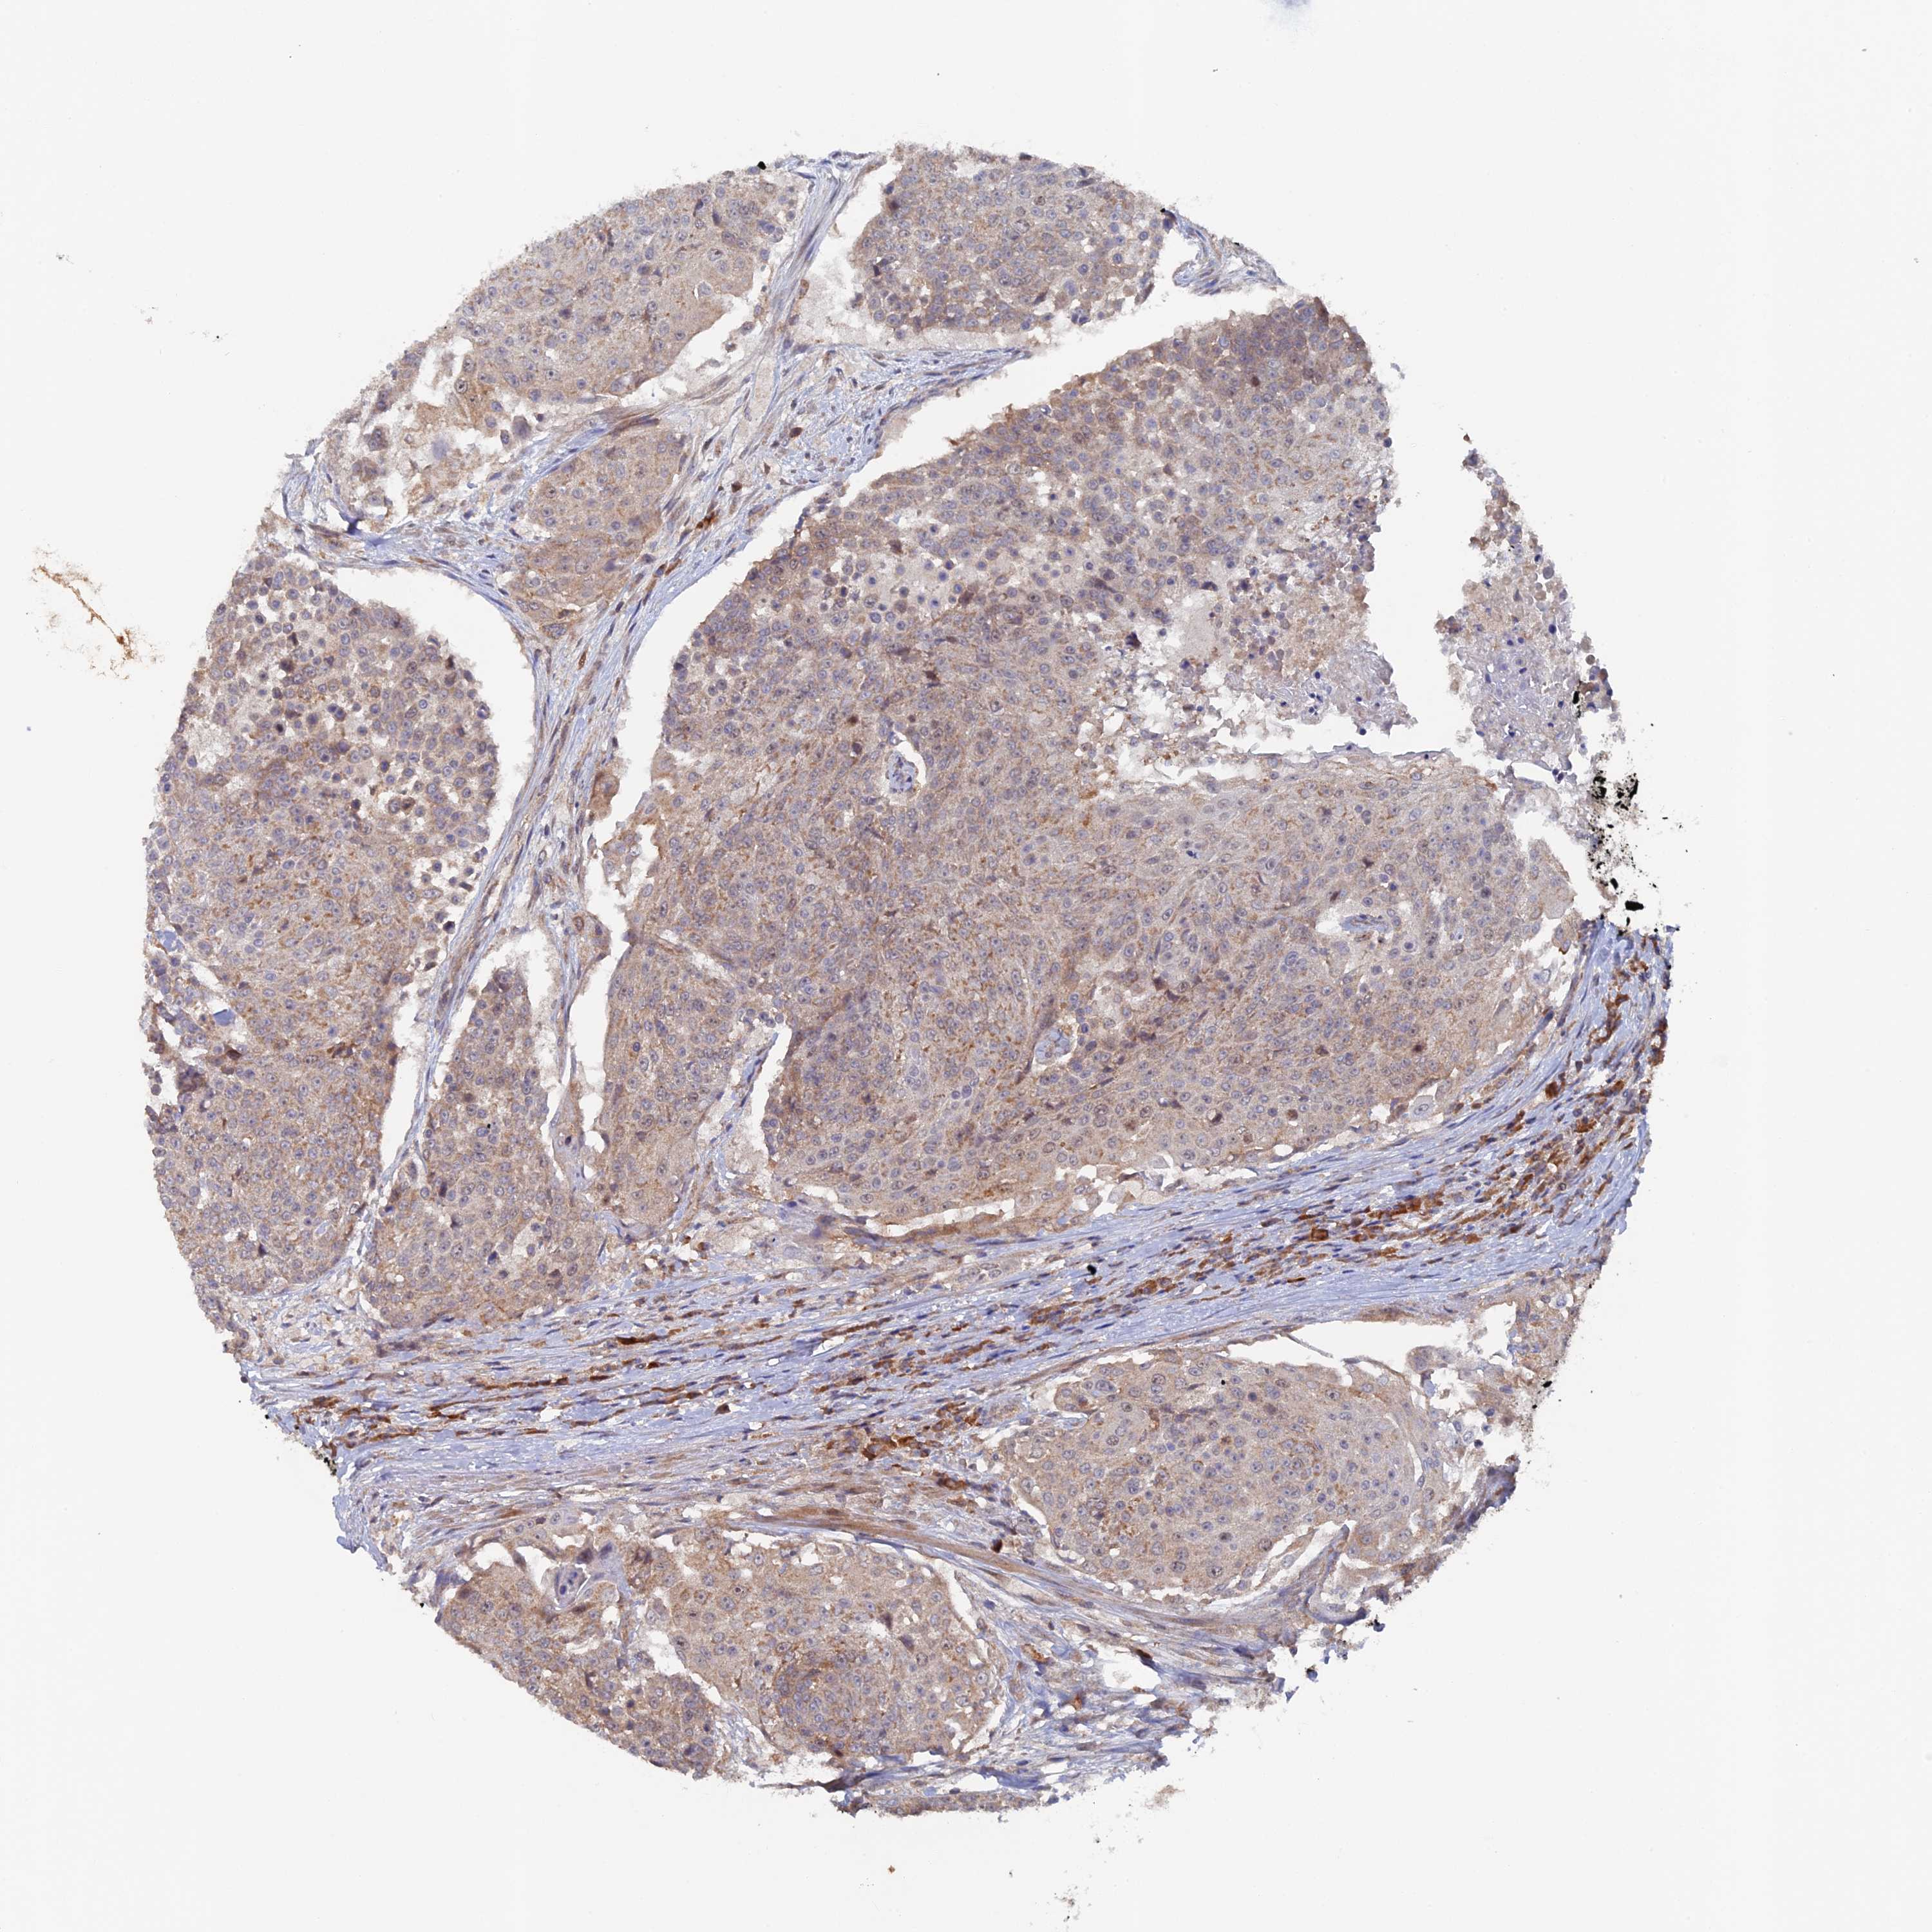

UROTHELIAL CANCER - Protein expressioni

A mouse-over function shows sample information and annotation data. Click on an image to view it in a full screen mode. Samples can be filtered based on level of antibody staining by selecting one or several of the following categories: high, medium, low and not detected. The assay and annotation is described here.

Note that samples used for immunohistochemistry by the Human Protein Atlas do not correspond to samples in the TCGA dataset.

Antibody stainingi

Antibody staining in the annotated cell types in the current human tissue is reported as not detected, low, medium, or high, based on conventional immunohistochemistry profiling in selected tissues. This score is based on the combination of the staining intensity and fraction of stained cells.

Each image is clickable and will lead to virtual microscopy that enables deeper exploration of all samples and also displays staining intensity scores, fraction scores and subcellular localization as well as patient and tissue information for each sample.

Antibody HPA041177

Staining

High

Medium

Low

Not detected

Intensity

Strong

Moderate

Weak

Negative

Quantity

>75%

75%-25%

<25%

None

Location

Nuclear

Cytoplasmic/membranous

Cytoplasmic/membranous,nuclear

Urothelial carcinoma, Low grade